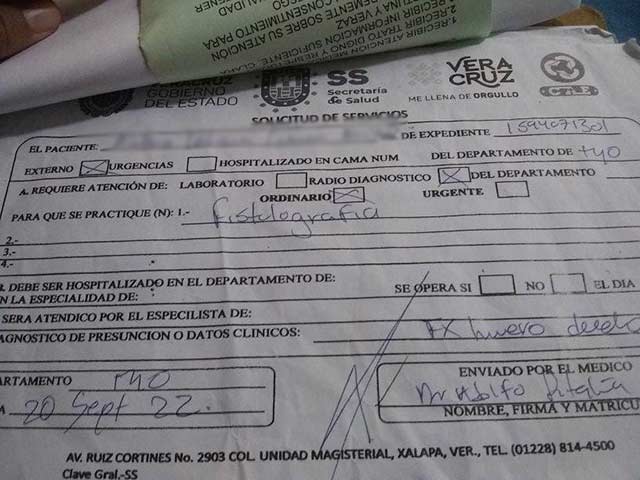

Me tienen que realizar una nueva cirugía por la infección que no se ha podido controlar pero para realizarla me piden un estudio que tiene en costo de $1,500 dinero, que por el momento no tengo. Estoy muy preocupada ya que los doctores me han dicho que si la infección no cesa y entre más tiempo deje pasar podría perder mi brazo.

Adjunto los documentos que constatan las intervenciones a las que he sido sometida y tarjeta en la cual puedo recibir de su ayuda a nombre de Julio Solorza y número de contacto 2283467611 por si alguien gusta apoyarme, lo que sea será bien recibido y con muchísimo agradecimiento.